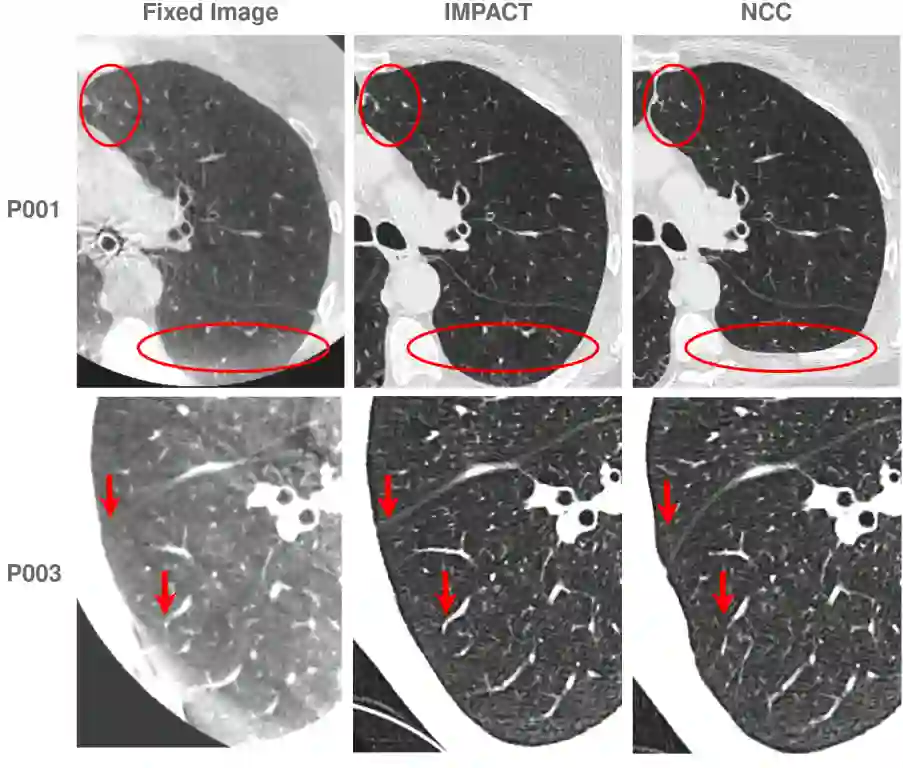

Image registration is fundamental in medical imaging, enabling precise alignment of anatomical structures for diagnosis, treatment planning, image-guided interventions, and longitudinal monitoring. This work introduces IMPACT (Image Metric with Pretrained model-Agnostic Comparison for Transmodality registration), a novel similarity metric designed for robust multimodal image registration. Rather than relying on raw intensities, handcrafted descriptors, or task-specific training, IMPACT defines a semantic similarity measure based on the comparison of deep features extracted from large-scale pretrained segmentation models. By leveraging representations from models such as TotalSegmentator, Segment Anything (SAM), and other foundation networks, IMPACT provides a task-agnostic, training-free solution that generalizes across imaging modalities. These features, originally trained for segmentation, offer strong spatial correspondence and semantic alignment capabilities, making them naturally suited for registration. The method integrates seamlessly into both algorithmic (Elastix) and learning-based (VoxelMorph) frameworks, leveraging the strengths of each. IMPACT was evaluated on five challenging 3D registration tasks involving thoracic CT/CBCT and pelvic MR/CT datasets. Quantitative metrics, including Target Registration Error and Dice Similarity Coefficient, demonstrated consistent improvements in anatomical alignment over baseline methods. Qualitative analyses further highlighted the robustness of the proposed metric in the presence of noise, artifacts, and modality variations. With its versatility, efficiency, and strong performance across diverse tasks, IMPACT offers a powerful solution for advancing multimodal image registration in both clinical and research settings.